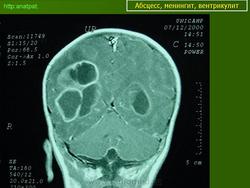

Абсцесс головного мозга – это очаговое скопление гноя в мозговом веществе, окруженное капсулой.

Абсцессы могут локализоваться в различных участках мозгового вещества. Обычно абсцессы сочетаются с менингоэнцефалитами, энцефалитами, сопровождаются повышением температуры тела, воспалительными изменениями крови и ликвора. Клиническая картина разнообразна и состоит из различных сочетаний общемозговых симптомов (головной боли, головокружения, тошноты, рвоты, нарушений сознания), менингеальной (оболочечной) и очаговой неврологической симптоматики.

Компьютерная (КТ) или магнитно-резонансная (МРТ) томография головного мозга являются ведущими методами диагностики посттравматических абсцессов, позволяющих судить об их расположении, объеме, структуре, консистенции, содержимом, воздействии на вещество головного мозга. Для исключения опухолей головного мозга, туберкулом, паразитарных заболеваний проводится ОФЭКТ (однофотонная эмиссионная компьютерная томография).